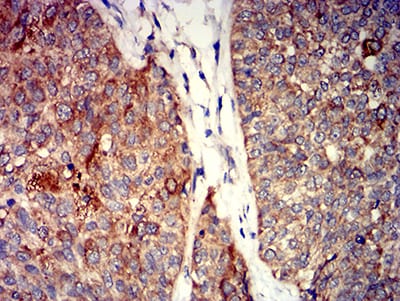

Immunohistochemical analysis of paraffin-embedded human cervical cancer tissues using GRIK4 mouse mAb with DAB staining.

Immunohistochemical analysis of paraffin-embedded human bladder cancer tissues using GRIK4 mouse mAb with DAB staining.